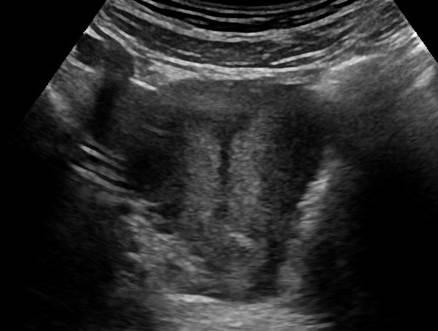

Dị dạng tử cung

Dị dạng tử cung - Ảnh 4

» Thông tin: Nữ giới – 14 tuổi.

» Lâm sàng: Kiểm tra sức khỏe.

# Tử cung có vách ngăn (Septate uterus).